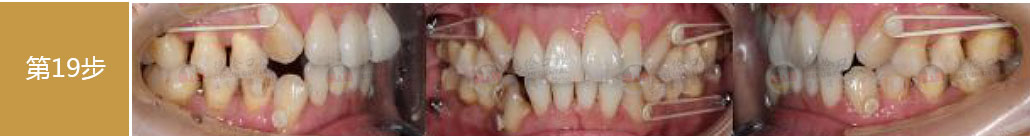

- 【診斷】

先天缺少下切牙2顆

上前牙錯(cuò)位于下前牙后側(cè),前牙無(wú)咬合功能,上牙槽及上唇后縮

打造醫(yī)生:德倫口腔正畸中心鄧毅醫(yī)生

- 【治療方案】

調(diào)整弓形及配合Ⅲ類牽引,實(shí)現(xiàn)頜跳躍

矯治前后對(duì)比

牙列整平排齊,前牙內(nèi)收;覆蓋、覆合正常;尖牙和磨牙達(dá)到中性關(guān)系;上下中線對(duì)齊;下頜后縮改善